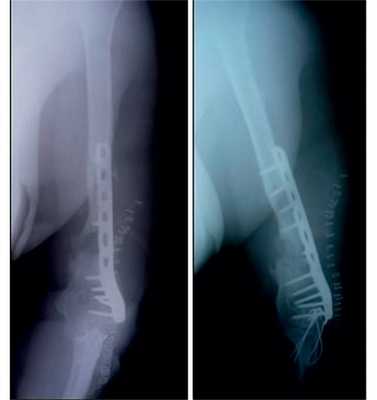

Клинический пример 2

Пациентка Н., 41 года.

Диагноз: ложный сустав левой плечевой кости.

На рис. 10-14 Рис. 10. Рентгенограмма пациентки Н. до операции. Рис. 14. Внешний вид и функция пациентки Н. через 8 мес после операции. представлены этапы обследования и лечения пациентки Н.

Рис. 11. Пациентка Н. Оперативное лечение: резекция зоны ложного сустава левой плечевой кости, остеосинтез пластиной и винтами. Пластика свободным кровоснабжаемым трансплантатом из внутреннего мыщелка бедренной кости.

Рис. 12. Рентгенограммы пациентки Н. после операции.

Рис. 13. Рентгенограммы пациентки Н. через 8 мес после операции.